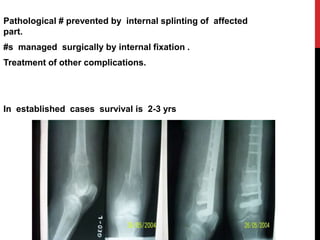

Pathological # prevented by internal splinting of affected

part.

#s managed surgically by internal fixation .

Treatment of other complications.

In established cases survival is 2-3 yrs